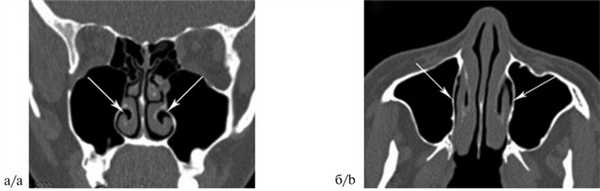

Больная В., 35 лет, 10 мая 2017 г. поступила в ЛОР-клинику ФБГОУ ВО «Ростовский государственный медицинский университет» Минздрава России с жалобами на затруднение носового дыхания. Считает себя больной в течение 8 лет. В течение этого периода неоднократно проводились ультразвуковая дезинтеграция ННР (в 2002, 2003 и 2015 гг.), внутрислизистая диатермокоагуляция ННР (в 2005 и 2009 гг.), курсовое физиотерапевтическое лечение, применялись топические стероиды. На СКТ носа и околоносовых пазух (рис. 3) был выявлен патологический изгиб ННР.

Рис. 3. Больная В., 35 лет. Компьютерная томограмма околоносовых пазух: коронарная (а) и аксиальная (б) проекции. Патологический изгиб обеих ННР (указано стрелками). Fig. 3. Patient V., aged 35 years. CT of the paranasal sinuses in the coronal (a) and axial (b) projections. The pathological bending of both inferior nasal turbinated bones (shown by arrows).

На основании результатов обследования выставлен диагноз: гипертрофический ринит, патологический изгиб ННР. В связи с этим была произведена двусторонняя нижняя конхотомия с захватом подвернутого свободного края ННР. Послеоперационный период протекал без осложнений. Больная выписана 15 мая 2017 г. При контрольном осмотре через 1 мес отмечено восстановление носового дыхания.